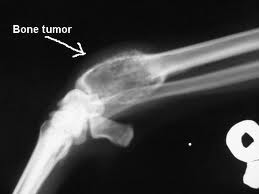

Bone cancer facts

- The majority of cancer involving the bones is metastatic disease from other remote cancers. Primary bone cancer is much rarer.

- Not all bone tumors are cancerous.